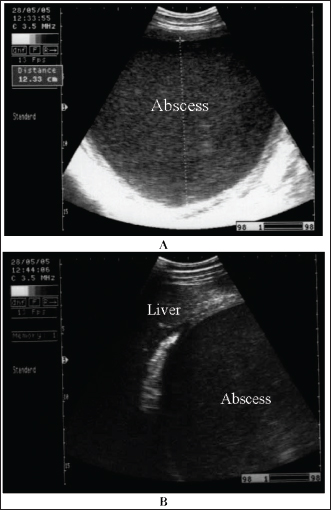

Abdominal abscesses

Intra-abdominal abscessation is not common in adult horses (Aleman et al., 2003; Recknagel et al., 2012) or in foals (Valdes and Johnson, 2005). In a 15-year-study, 40 horses with intra-abdominal masses were studied; 3 of them (7.5%) had mesenteric abscesses (Recknagel et al., 2012). The pathogenesis of abdominal abscessation in horses is presumably similar to that in ruminants (Aleman et al., 2003). It was not possible to determine the cause of the abdominal abscess in the present case. In addition, in equines, the abscess likely formed as a direct extension of a hematogenous infectious process, similar to the development of mesenteric abscess in a bull with chronic peritonitis (Elce, 2006). Several pathogens are considered causative agents of abdominal abscessation, such as Rhodococcus equi, Streptococcus equi subsp. equi, Corynebacterium pseudotuberculosis, Clostridium novyi type A, Blastomyces dermatitidis, and Fusobacterium necrophorum. Pseudomonas aeruginosa can also induce mesenteric abscesses in equines (Arnold et al., 2012; Tharwat et al., 2024c). Equines with abdominal abscesses are usually admitted with a history of fever, weight loss, colic, inappetence, and signs of depression of various durations (Tharwat et al., 2024c).

Abdominal abscess was strongly suspected on the basis of ultrasonographic findings (Fig. 20). The differential diagnoses include abdominal neoplasia. Ultrasonography is also useful for percutaneous needle aspiration for bacteriologic evaluation and facilitates intralesional antibiotic treatment and drainage because the thick abscess capsule prevents the spread of antibiotics (Tharwat et al., 2024c) (Figs. 21 and 22). For large abscesses, transcutaneous aspiration of pus should be performed under ultrasound guidance, as reported in cattle (Mohamed et al., 2002; Mohamed et al., 2003a,b,c; Mohamed and Oikawa, 2008). The ultrasound-guided percutaneous drainage of abdominal abscesses has several advantages. First, the animal should not be anesthetized. Second, surgery is not required, and consequently postoperative drawbacks will not develop. Third, percutaneous drainage is typically cost-effective. Fourth, percutaneous ultrasound-guided drainage can be performed promptly after diagnostic ultrasound is performed because the methodology does not require any particular planning or preparation and can be completed quickly if the examiner is experienced. Complications associated with ultrasound-guided percutaneous aspiration of the abscess in the present case were not encountered (Tharwat et al., 2024c). Follow-up after pus aspiration confirmed the treatment response, reduction in abscess size, and recovery (Figs. 23 and 24).

Fig. 20. Ultrasonograms of an 8-year-old Thoroughbred mare with abdominal abscess. Image A shows a sonogram obtained at admission (day 0) in which a mass with a thick echogenic capsule with homogenous and echogenic internal contents was identified. The mass was located close to the liver, deforming its right lobe margins B.

Fig. 21. Ultrasonograms of an 8-year-old Thoroughbred mare with abdominal abscess. Image A shows the fine-needle aspiration technique used to drain the content of the abscess. Image B an ultrasound-guided aspiration of pus from an abdominal abscess.